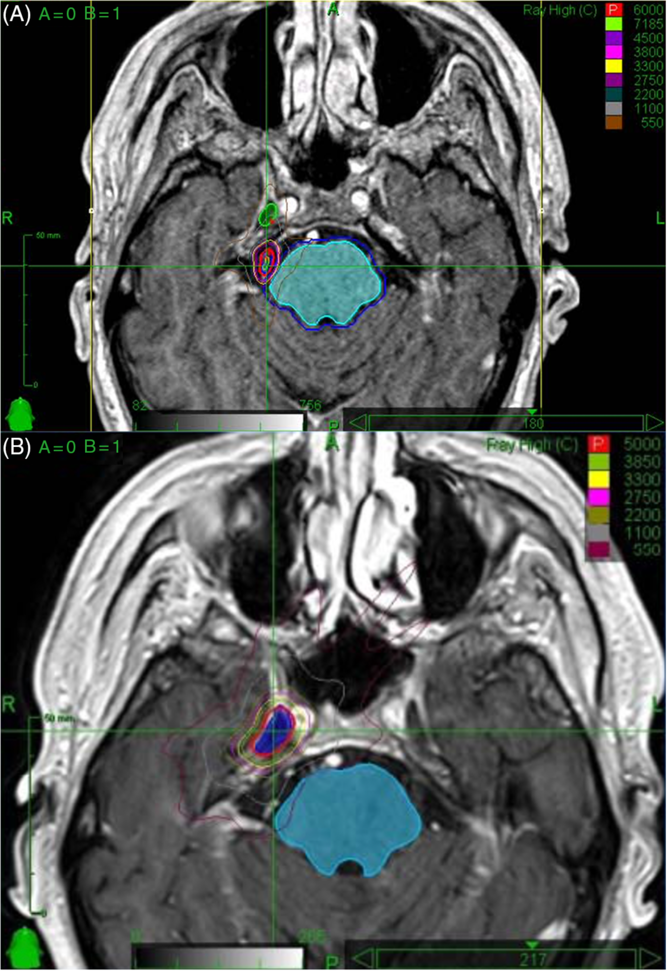

The patient had a past history of right-sided, medically refractory trigeminal neuralgia. He presented initially with episodes of severe, lancinating right-sided facial pain and continued to have symptoms despite treatment with carbamazepine. The decision was made to undergo stereotactic radiosurgery. He was treated with 60 Gy of CyberKnife radiosurgery in April 2013 (see Figure 1 for radiation planning images). The radiation was predominantly delivered to the right preganglionic trigeminal nerve, with 14 Gy targeted to the Gasserian ganglion. His initial response was positive despite some mild hemifacial numbness. After progression of symptoms 2 years later, he was having up to 15 episodes of pain daily. Repeat magnetic resonance imaging (MRI) at the time was unremarkable. He underwent an additional 50 Gy of irradiation to the right Gasserian ganglion in December 2015 (see Figure 1 for radiation planning images) and unfortunately developed significant right hemifacial numbness in V 1-3. His pain continued to progress and became more constant rather than episodic.

Figure 1: (A) Radiosurgery planning images for first treatment in April 2013. The mesial temporal lobe, depending on the location, received up to 5.5 Gy. In the area of suspected radiation necrosis (Figure 2), there was minimal radiation received from this treatment. (B) Radiosurgery planning images for second treatment in December 2015. The mesial temporal lobe, depending on the location, received up to 33 Gy. In the area of suspected radiation necrosis (Figure 2), there was up to 11 Gy received from this treatment.

A literature review identified one previously reported case of radiation necrosis following stereotactic radiosurgery for trigeminal neuralgia.Reference Montoure, Zaidi, Sheehy, Shetter and Spetzler5 In Montoure et al.’s report, the patient had undergone TomoTherapy for trigeminal neuralgia 1 year prior to the development of a ring-enhancing lesion in the mesial temporal lobe (Table 1). The authors performed a supratotal resection of the lesion and a final diagnosis of radiation necrosis was made based on histological examination. When comparing the two cases, a number of differences and similarities are noted. Both patients were treated with stereotactic radiosurgery for refractory trigeminal neuralgia. Montoure et al’s case involved a total of 40 Gy of TomoTherapy radiation in two equally divided doses; our patient underwent a total dose of 110 Gy of CyberKnife radiation divided in two unfractionated doses 2 years apart; the mesial temporal lobe, depending on the location, received up to 5.5 Gy on the first treatment and up to 33 Gy in the second treatment – after analyzing the radiosurgery treatment plans, it appears that the area of suspected radiation necrosis likely received minimal radiation from the first treatment and up to 11 Gy from the second treatment (Figure 1). Both patients developed symptoms within 1–2 years. MRI findings were nearly identical. Montoure et al.’s case was diagnosed with tissue biopsy, while this case was diagnosed by a combination of clinical characteristics and radiographic evidence (MRI and MRS). A comparison is summarized in Table 1.